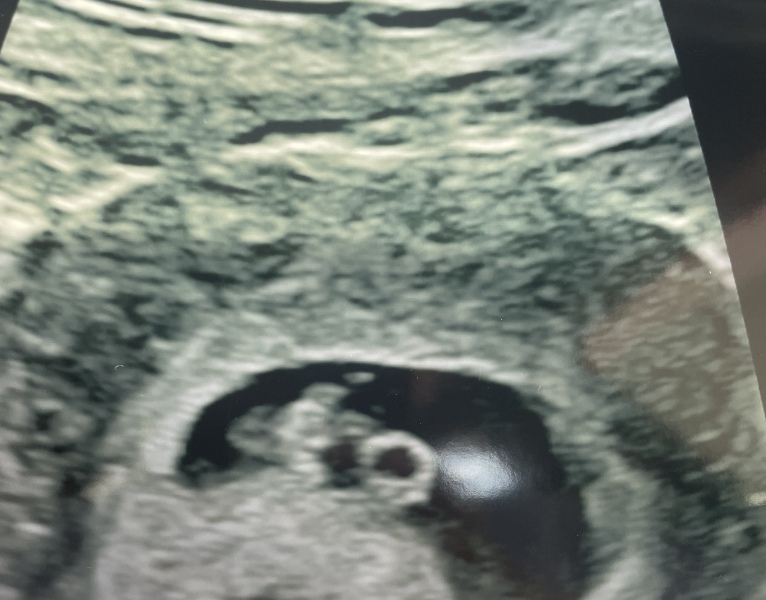

Mummy1502 · 09/05/2023 19:41

Everything is fine, measuring 7+4 x

6dpo positive pregnancy test

@Mummy1502 ohh look at that little bean! Makes me happy! I’m so pleased everything is ok. I’m sure you feel so much better now ❤️